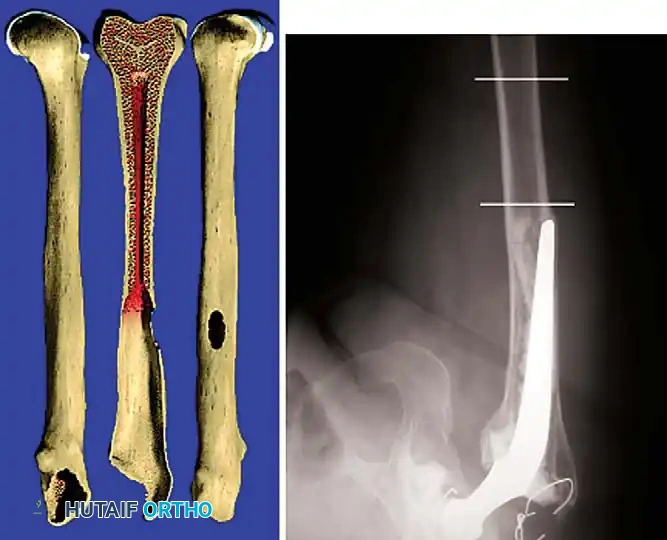

The Extended Trochanteric Osteotomy (ETO)

For complex femoral revisions, particularly those involving well-fixed cementless stems, varus remodeling, or extensive distal cement mantles, the Extended Trochanteric Osteotomy (ETO) is the gold standard.

Biomechanics of the ETO:

Unlike a standard trochanteric osteotomy, the ETO preserves the insertion of the gluteus medius and minimus proximally, and the origin of the vastus lateralis distally. This maintains a continuous myofascial sleeve, providing dynamic stability to the osteotomy fragment and dramatically improving union rates (typically >95%).

ETO Technique:

1. Measure the required length of the osteotomy preoperatively (usually 12-15 cm, ensuring it bypasses the well-fixed portion of the stem).

2. Elevate the vastus lateralis anteriorly to expose the lateral femur.

3. Use an oscillating saw or high-speed burr to make the posterior and anterior longitudinal cuts.

4. Complete the distal transverse cut, ensuring rounded corners to prevent stress risers.

5. Lever the fragment open anteriorly, hinging on the intact anterior periosteum and vastus lateralis.